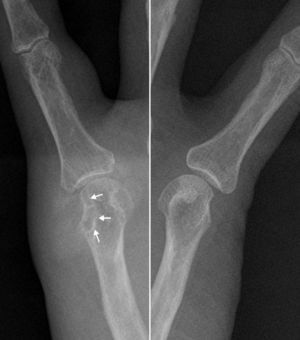

The ultrasound showed no effusion, but found a soft tissue injury, partially defined, and heterogeneous echotexture with hyperechoic areas. The tumor was in contact with the cortical bone of the metacarpal, which remained intact, except for an area where we observed a marked erosion, with a soft tissue lesion projecting into the medullary cavity (Fig. 1). Given the ultrasonography findings, X-rays were analyzed, confirming increased periarticular soft tissues, with very high density, accompanied by erosion of the metacarpal head, which as a hallmark had a sclerotic margin (Fig. 2). These sonographic and radiographic findings indicated periarticular tophi associated with bone erosion. The ultrasound-guided arthrocenthesis of the tophus showed a dense whitish material that under polarized light microscopy was identified as monosodium urate crystals (Fig. 3).

X-rays centered on the fifth metacarpophalangeal joint of both hands that allows for the assessment of the bone erosion comparatively and shows the sclerotic margin (arrows) with soft tissue augmentation and high density in the medial aspect of the right metacarpal head. There was no involvement of the joint space.